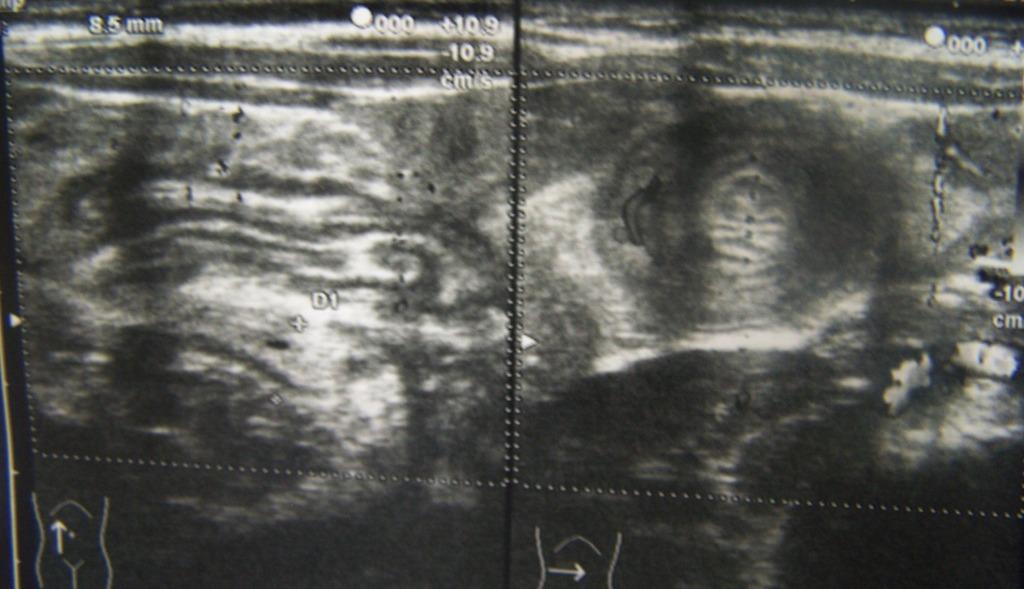

L�ecografia dell�addome si esegue con qualche difficolt� per la scarsa collaborazione della piccola. Il quadro ecografico � il seguente: pancreas, reni, fegato e milza nella norma per ecostruttura ecogenicit� e dimensioni. Vescica semivuota. Peristalsi intestinale vivace a sx, assente a destra ove si evidenzia, fra il margine inferiore del fegato e il rene, una grossa formazione con forma a bersaglio in scansione traversa all�asse principale, e forma reniforme in scansione longitudinale. La �massa� presenta pareti ispessite, prevalentemente iperecogene al centro, ipoecogene in periferia e discreta vascolarizzazione sia all�interno che all�esterno. Nel contesto della massa si evidenziano due-tre linfonodi ipoecogeni di volume lievemente aumentato con � max di mm 6. A sinistra le anse intestinali sono regolari (Figura 1).

Figura 1. Scansione ecografica longitudinale ( a sx) e traversa (a dx) prima del clisma di acqua